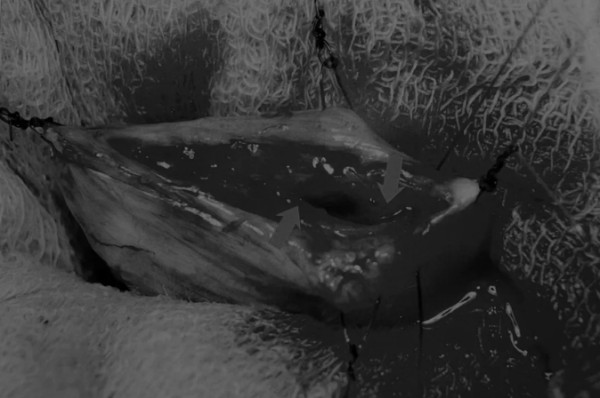

在中线开腹手术后,确定膀胱,将其取出并隔离(图1)。为了使膀胱持续暴露,可在膀胱中线两侧各放置一根固定缝线(图2)。

图1 将膀胱从腹腔中取出,用无菌外科敷料隔离。为了防止膀胱滑入腹部,可在膀胱顶部放置一根固定缝线,由助手通过止血钳夹住固定缝线做持续牵引